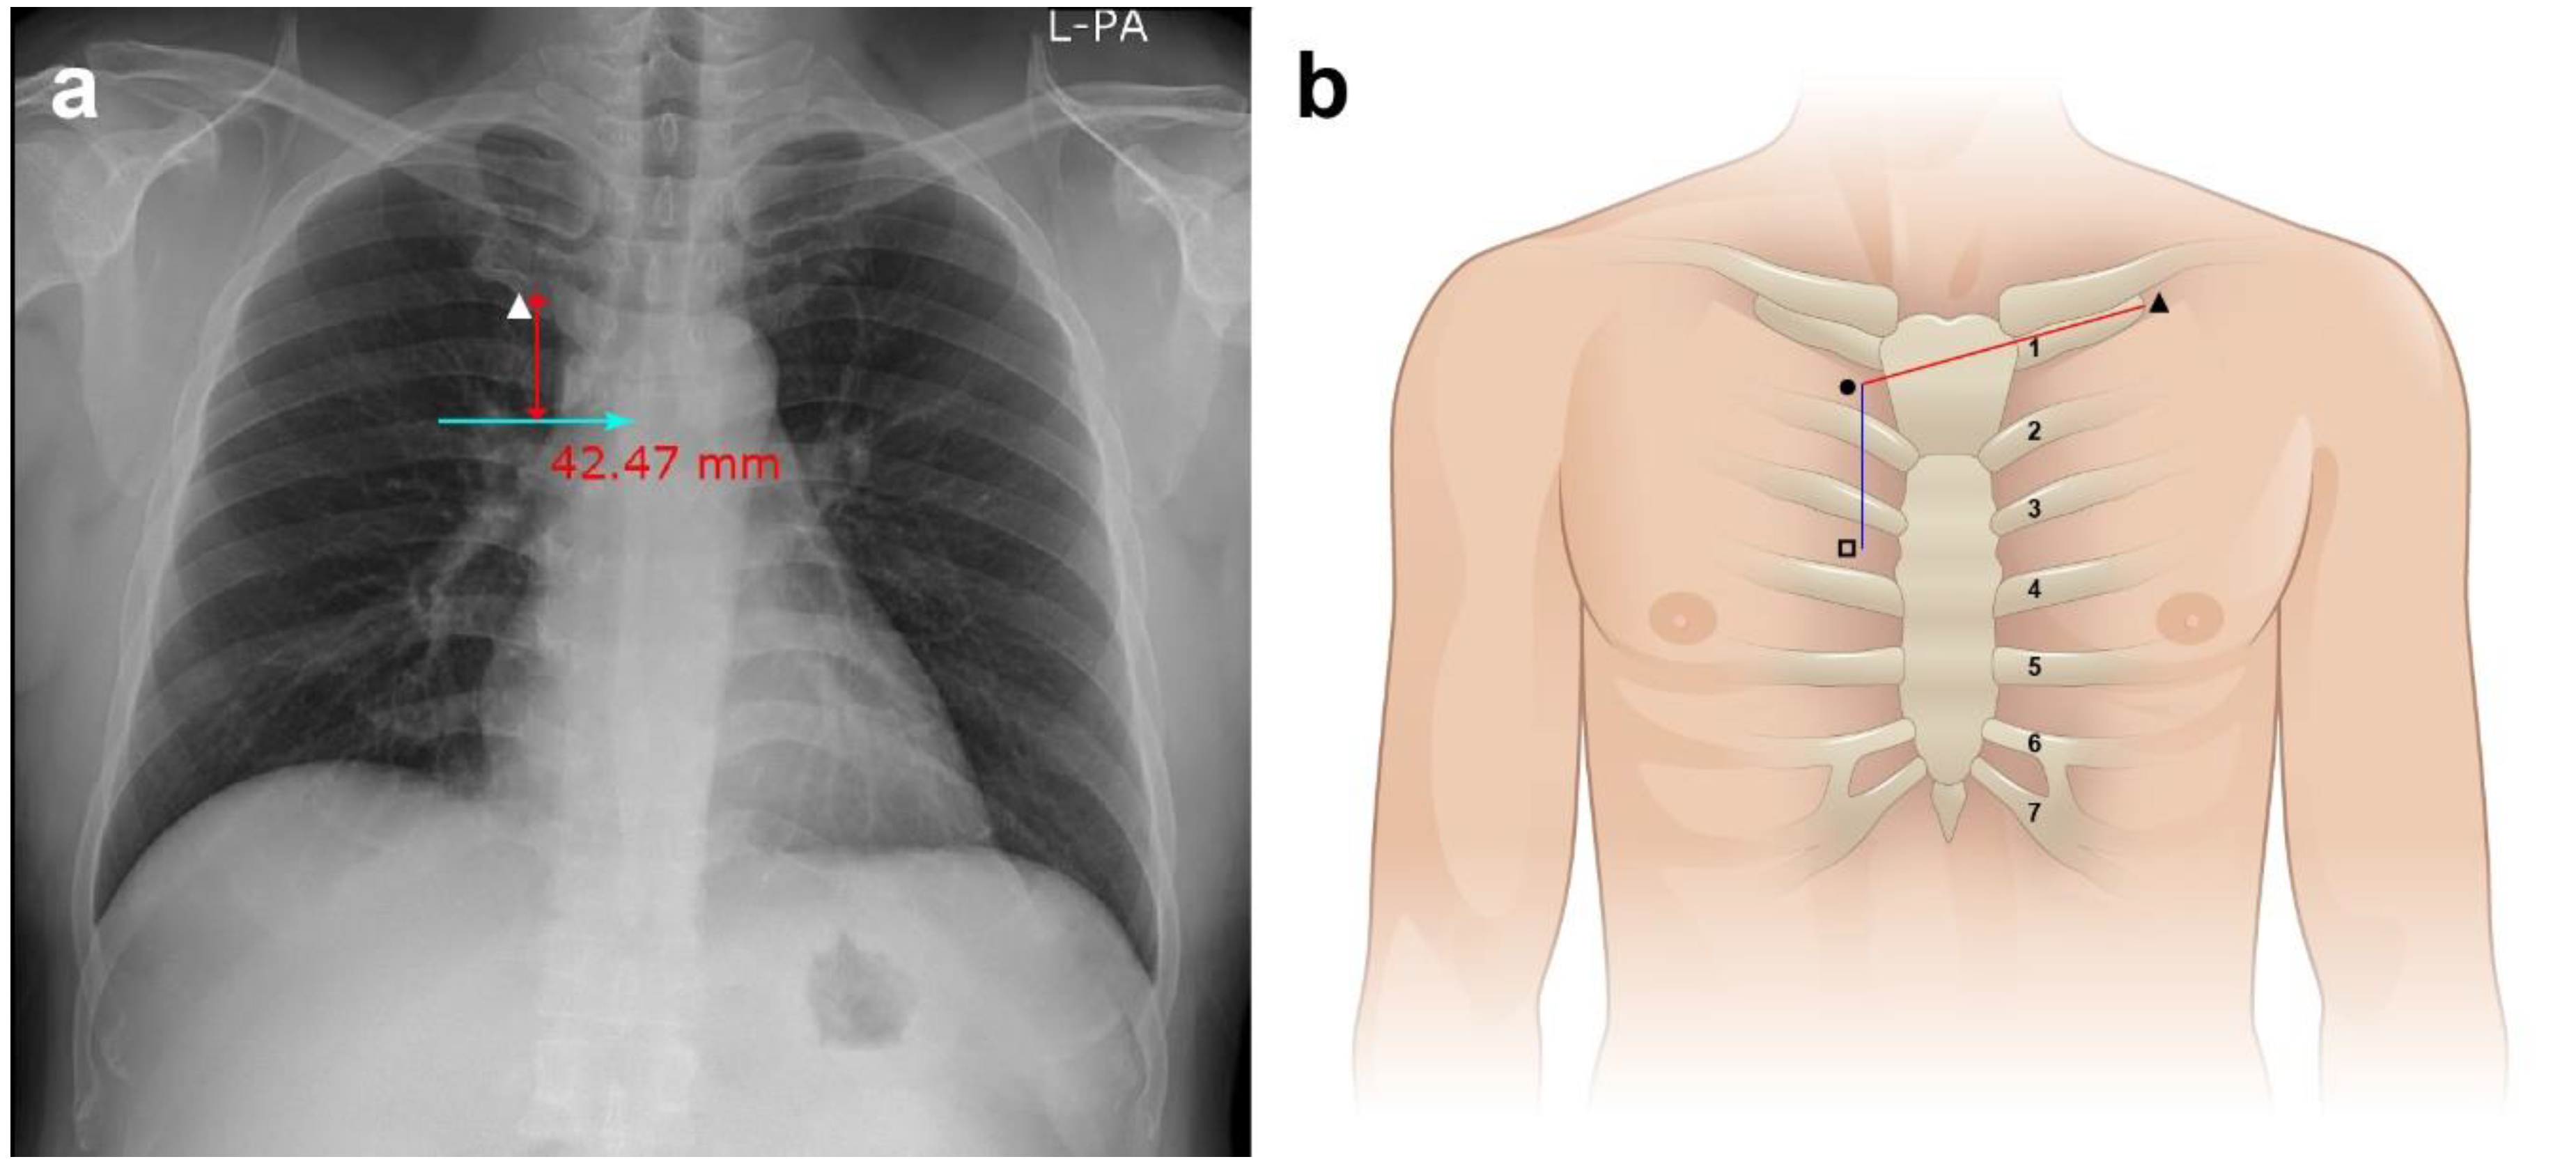

2.3. Procedure and Data Collection